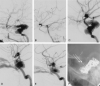

Background and purpose: Endovascular techniques are the methods of choice for the treatment of patients with carotid cavernous fistulas. We report our experience using stent-assisted coil placement for treatment of patients with high-flow fistulas that are associated with severe laceration of the internal carotid artery.

Methods: In a retrospective review of an internal endovascular therapy database covering the interval between October 2001 and October 2003, we identified a total of 5 patients presenting with 6 high-flow type A carotid cavernous fistulas (one had a bilateral fistula) that were associated with severe laceration of the internal carotid artery. All were treated first with stenting of the injured segment of the internal carotid artery followed by transarterial (3/6) and/or transvenous (4/6) obliteration of the fistula with detachable platinum coils. In 2 cases, a liquid adhesive was also used. In all instances, a compliant balloon was inflated within the stented arterial segment during coil deposition to avoid extension of coils into the parent artery.

Results: All 6 fistulas were obliterated, and each internal carotid artery was successfully reconstructed. Except for posttraumatic cranial nerve dysfunction in 1 patient, clinical outcome was very good. Follow-up angiograms in 3 of the 6 patients obtained at intervals between 3 and 6 months (mean, 4.5 months) revealed no fistula recurrence and no evidence of intimal hyperplasia within the stent.

Conclusion: In this series of patients with high-flow carotid cavernous fistula associated with severe injury to the internal carotid artery, stent-assisted coil placement offered a safe and effective treatment. Stent-assisted coil placement may increase the ability to successfully treat fistulas with severe injury to the internal carotid artery with preservation of the parent artery.